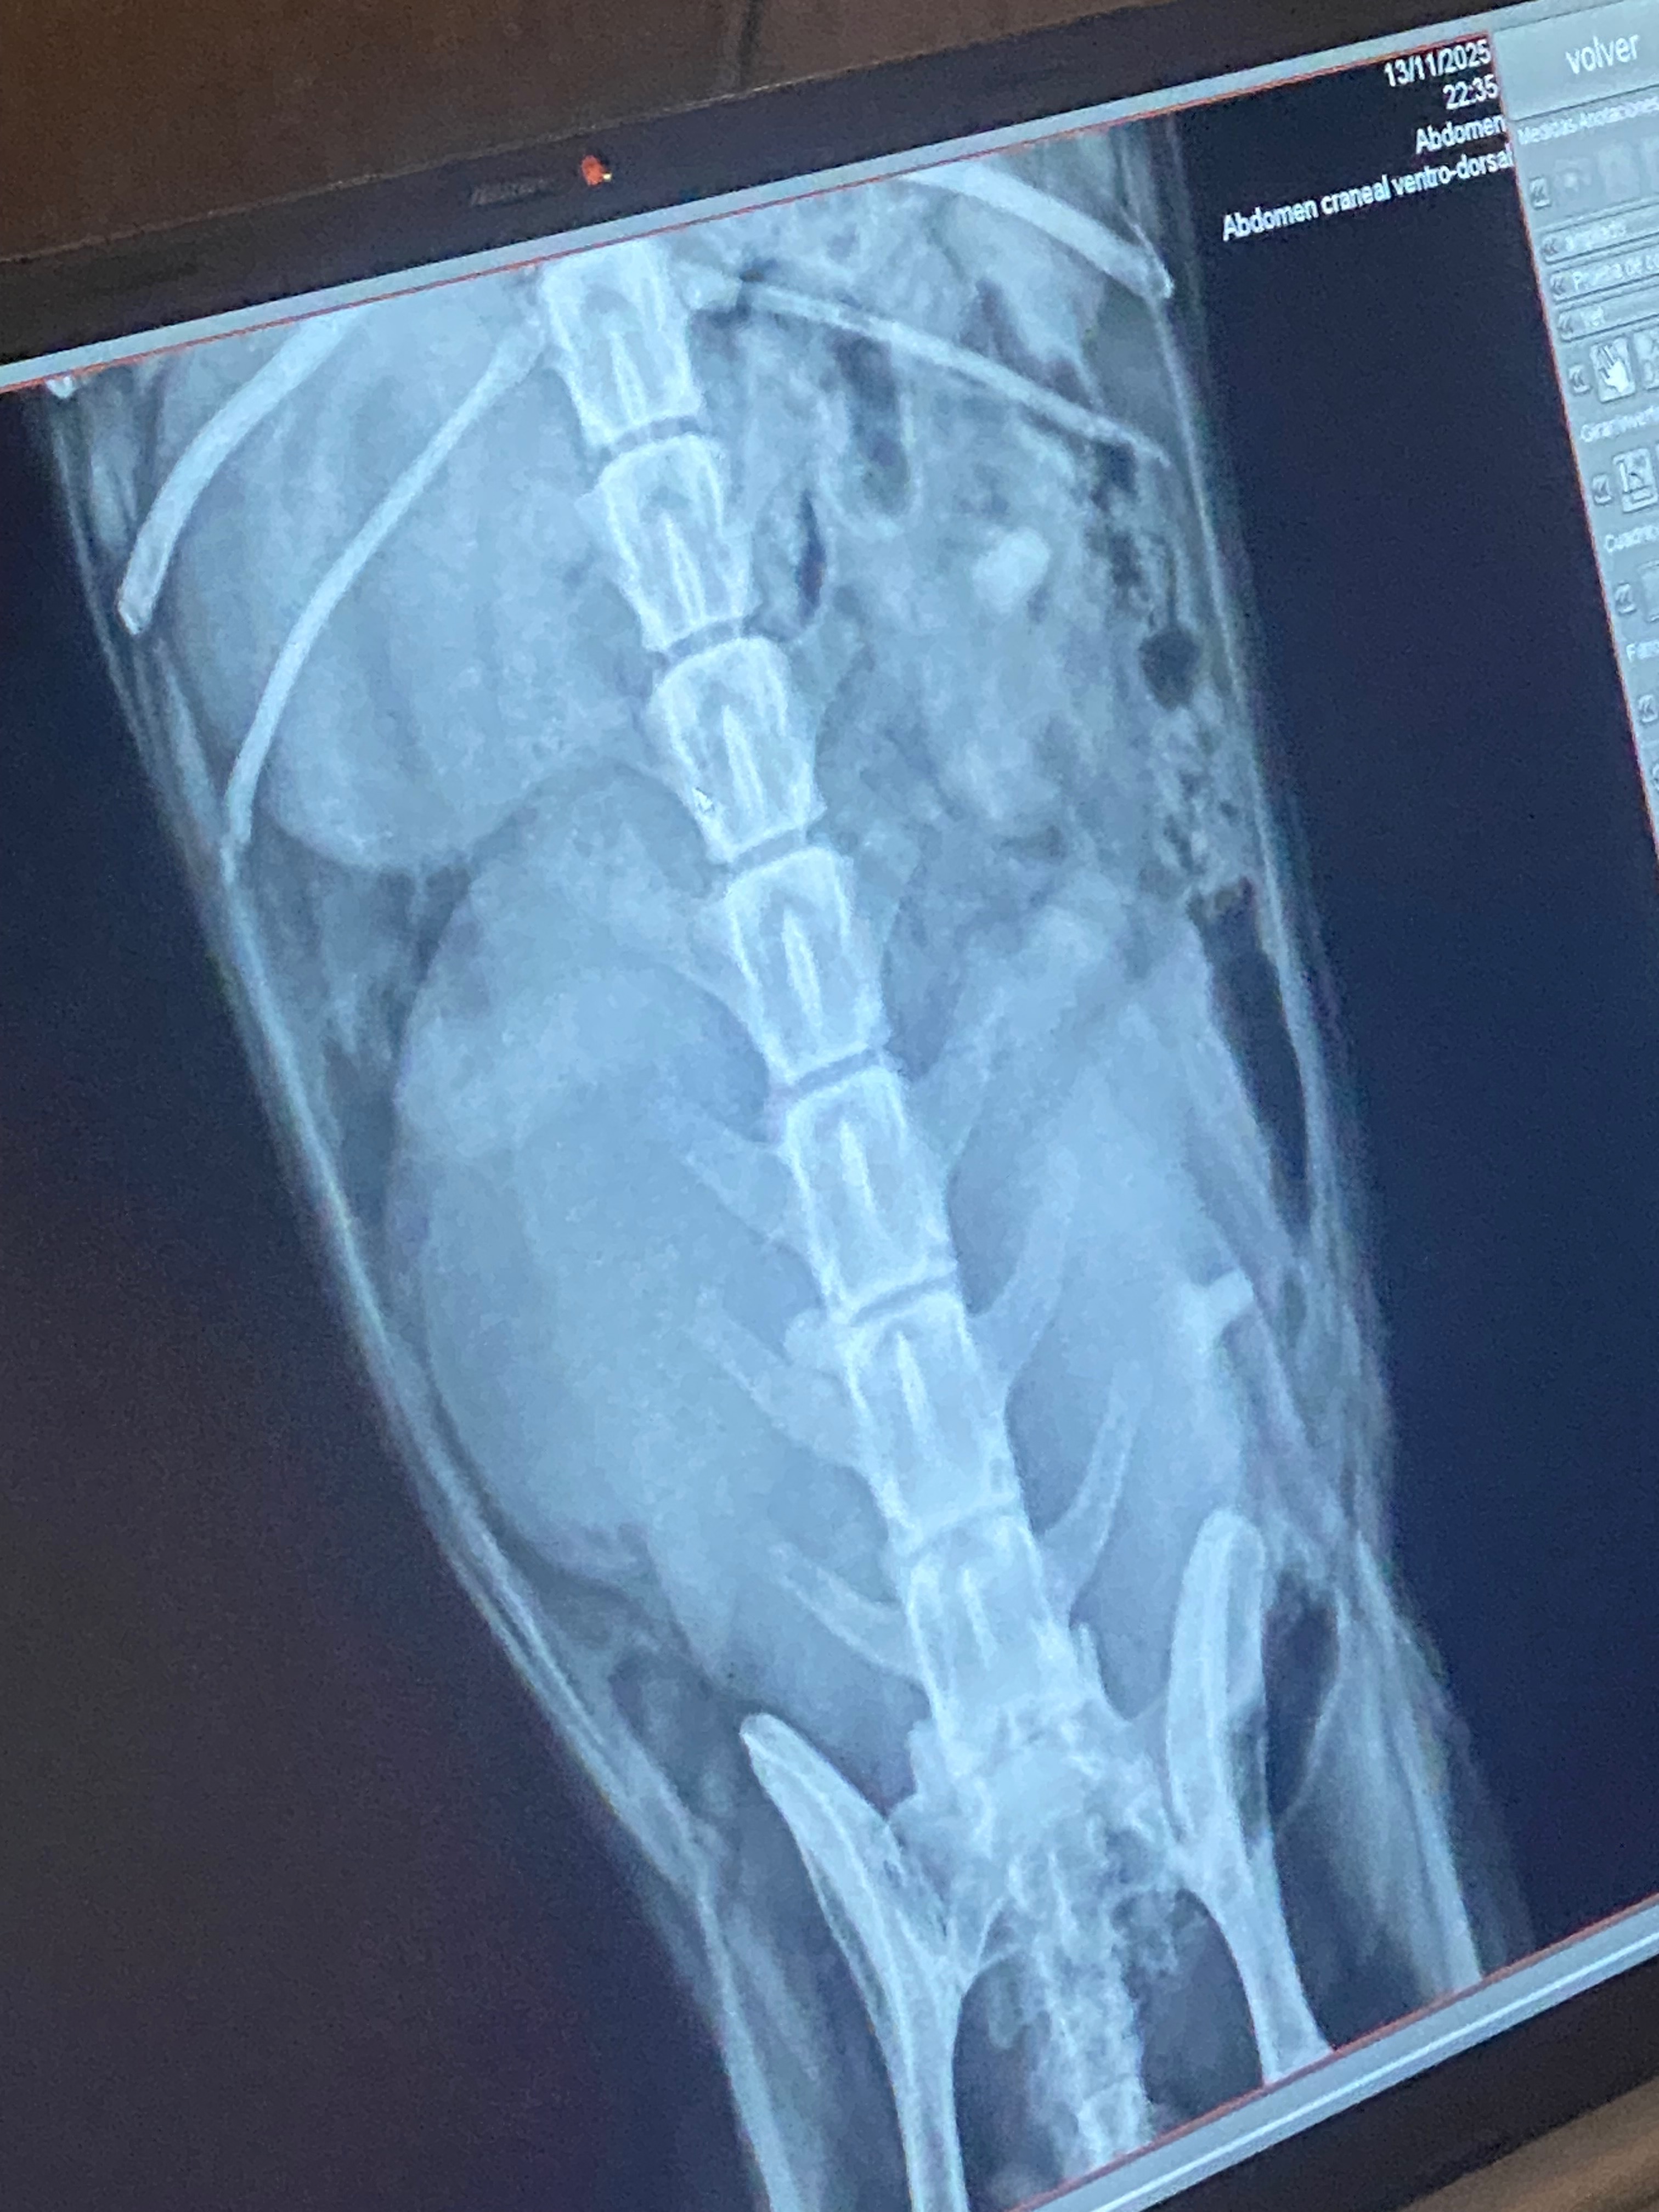

Recently, Joey developed a mass that has grown rapidly over the past few weeks. Despite following a treatment plan in hopes that it would shrink, the mass has doubled in size and is now crushing her bladder and other vital organs. The cause of the mass is still unknown, and the only way to find out is to have it removed and sent to a lab for testing. Her situation is urgent, and surgery is the only option to save her life.